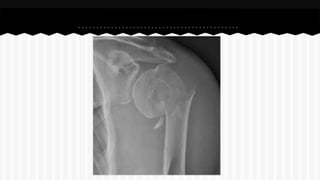

RESPONDA O NOME DO OSSO EM QUE

SE ENCONTRA A (S) FRATURA (A).